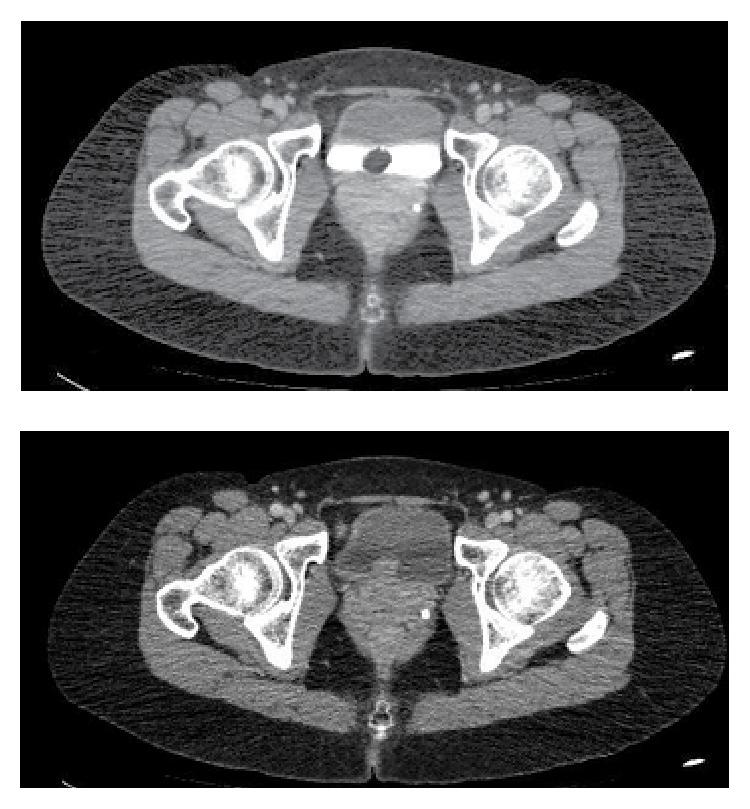

Primary mucinous adenocarcinoma is an extremely rare type of bladder cancer, with aggressive behavior and poor response to chemotherapy and radiotherapy. The symptoms are similar to those of other bladder tumors. Surgery is the main treatment and remains the only curative option. There may be a progression from mucinous metaplasia to mucinous adenoma and then mucinous adenocarcinoma. We present the case of a 40-year-old woman with recurrent lower urinary tract infections, submitted to imaging tests, which showed a bladder tumor. After transurethral resection, pathology showed intestinal mucinous carcinoma. Metastatic work-up was negative. New surgical procedure showed metaplasia but no recurrence of the carcinoma. The patient is now using antibiotic prophylaxis and will undergo a cystoscopy every 3 months and computed tomography in one year.

原发性黏液腺癌是一种极为罕见的膀胱癌类型,具有侵袭性,对化疗和放疗反应不佳。其症状与其他膀胱肿瘤相似。手术是主要治疗方法,也是唯一的治愈选择。可能存在从黏液化生发展为黏液腺瘤,进而发展为黏液腺癌的过程。我们报告一例40岁女性,反复出现下尿路感染,接受影像学检查显示膀胱肿瘤。经尿道切除术后,病理显示为肠道黏液癌。转移评估为阴性。再次手术显示为化生,但癌未复发。患者目前正在进行抗生素预防,每3个月将接受一次膀胱镜检查,一年后进行计算机断层扫描。